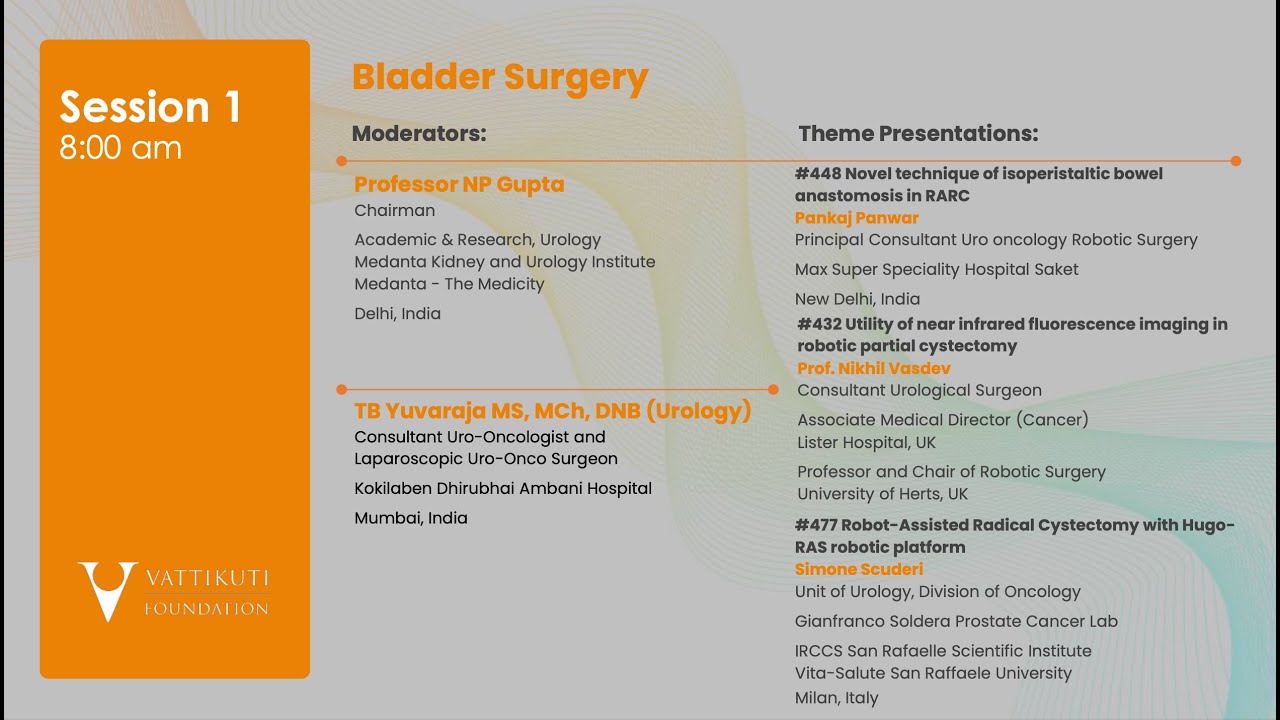

Jaipur Saturday Session 1 Bladder Surgery